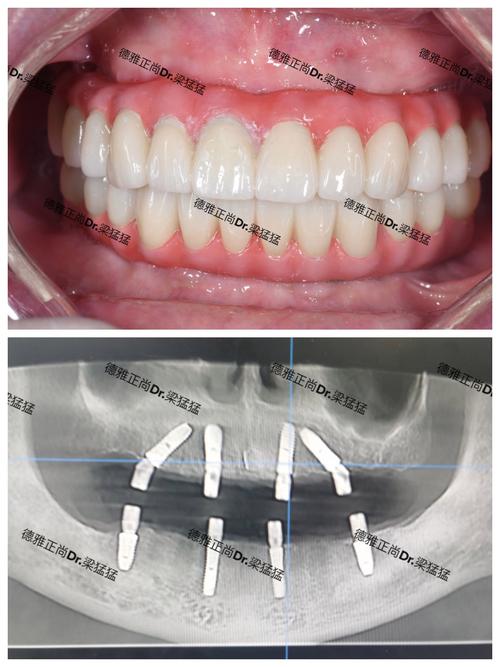

- 种植牙需要在牙槽骨内精确植入人工牙根(种植体),位置、角度、深度都有严格要求,偏差可能导致种植失败、神经损伤、上颌窦穿孔等并发症。

- 常需要借助CBCT(锥形束CT)等影像学数据进行术前设计和术中导航,对医生的技术和经验要求很高。

- 术中风险: 出血、神经损伤(下牙槽神经、颏神经)、上颌窦穿孔、邻牙损伤、种植体植入位置不佳等。

- 术后风险: 伤口感染、种植体周围炎、种植体松动或失败、骨结合不良、感觉异常(麻木)、疼痛等。

(图片来源网络,侵删)- 种植区域紧邻重要的解剖结构,如:

- 下颌管: 内含下牙槽神经血管束,损伤会导致下唇、颏部麻木。

- 颏孔: 有颏神经穿出,损伤会导致局部麻木。

- 上颌窦: 在上颌后牙区,种植体可能穿入上颌窦,导致感染或种植失败。